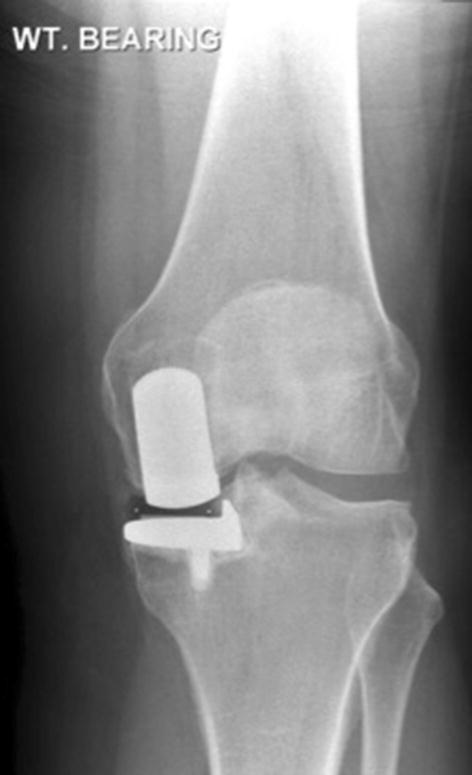

In 60 (67%; Table 3) pre-revision radiographs, a reason for revision was not identified. Common causes for revision were lateral compartment arthritis (10%), aseptic loosening (10%), and dislocation (7%). Infection was the cause for revision in 6% as spacers were seen on the post-revision radiographs. Other causes included peri-prosthetic fracture (2%, one femoral, one tibial) and gross component mal-alignment (2%). However, some cases had malaligned radiographs that made the implant look malaligned and malpositioned, but looked well aligned and positioned on aligned films (Fig. 6).

Fig. 6.

Radiograph on the left demonstrating what appears to be significant medial overhang and malalignment of the tibial component. A subsequent aligned radiograph of the same knee demonstrating a perfectly aligned tibial component. Note the presence of excess cement in and around the joint

There was variability in the quality of post-operative radiographs. It is recommended that anteroposterior radiographs are aligned to the tibial component, and lateral radiographs aligned to the femoral component [6]. On malaligned radiographs correctly positioned components may appear mal-positioned or malaligned (Fig. 6), and this may incorrectly be interpreted as a cause of pain. A problem peculiar to the Oxford Knee is that the posterior part of the tibial component is wider than the tibia to support the bearing in high flexion. Therefore, with malaligned radiographs postero-medial tibial overhang is often seen but there is no evidence that this causes pain and it not a justification for a revision (Fig. 6). In contrast with well aligned radiographs if tibial overhang is seen this means there is medial overhang in the region of the MCL, which, if extensive, can cause pain and be a justification for revision [4]. The only way to be certain if there is component loosening is if there is component migration. To assess migration requires two sequential radiographs to be taken in an identical fashion, which requires aligned radiographs. The assessment of the bone implant interface and whether a radiolucency is physiological or pathological can also only be done with an aligned radiograph. With an oblique view the interface is obscured (Fig. 7). It is, therefore, important that radiographers are taught how to take aligned radiographs [14].